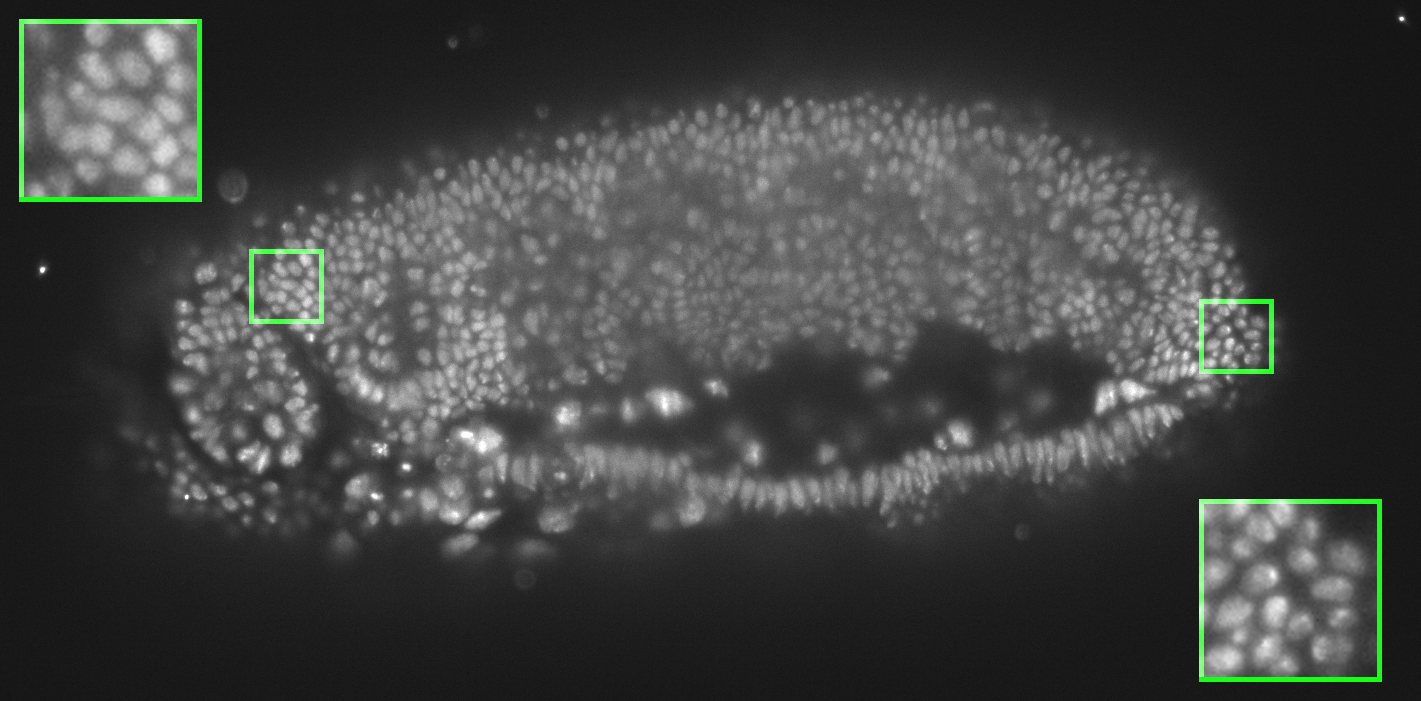

As mentioned above, it is hard (any potentially undesirable) to directly build a GDP from biomedical images. We hence learned the prior from natural-scene images, but validate it here on biomedical images. We first show stability of the present GDP for biomedical images. For this, we collected a small dataset of biomedical images, including X-ray, MRI, electron microscopy, and fluorescence microscopy images. Some examples are shown in Figs. 10 and 24.

9.1 Image naturalization

Remapping the gradient field of any image to match the GDP of natural-scene images, and then reconstructing the output image is called image naturalization, because the output image will have a gradient distribution that matches the one of natural-scene images. The naturalized output image hence looks more “natural”. The workflow is shown in Fig. 23. Since the GDP correlates with image quality, this makes the image look more appealing. We hence propose to use image naturalization as an alternative to histogram equalization when displaying images to a human observer. Image naturalization enhances contrast by solving Eq. 2 with hard GDP constraint. Some examples of microscopy images (left tile of each panel) and their naturalized versions (middle tiles) are shown in Fig. 24 along with the naturalness factor of the original image. The histogram-equalized images are shown in right tiles for comparison. The first row shows four fluorescence-microscopy images. The second row shows three electron-microscopy images and one fluorescence image. All images were collected from publicly accessible web pages; credits are in parentheses. Here we use the simple linear function, amounting to a straightforward rescaling of the image, albeit with a good, “natural” scale factor as determined by the GDP. In all cases. the naturalized image looks more appealing than the histogram-equalized image, and suffers from less background artifacts.